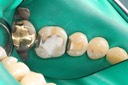

Gary Umeda #3,4,5 pre-op

Gary Umeda #3-4 pre-op